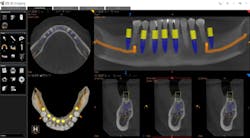

Figure 5: Virtual planning of immediate implant placement

In today’s practice, dental professionals should have imaging that can satisfy all their diagnostic needs. CBCT is an investment that generates a strong return, especially when it covers nearly every routine situation as well as more advanced clinical situations (figure 6). With the systems currently available, you can cost-effectively take the essential first step with 2-D panoramic views and investigate in depth with powerful 3-D imaging. As a result, you can offer and perform more procedures in your practice, improving the overall level of patient care.

Figure 6: A full-mouth implant reconstruction achieved with CBCT